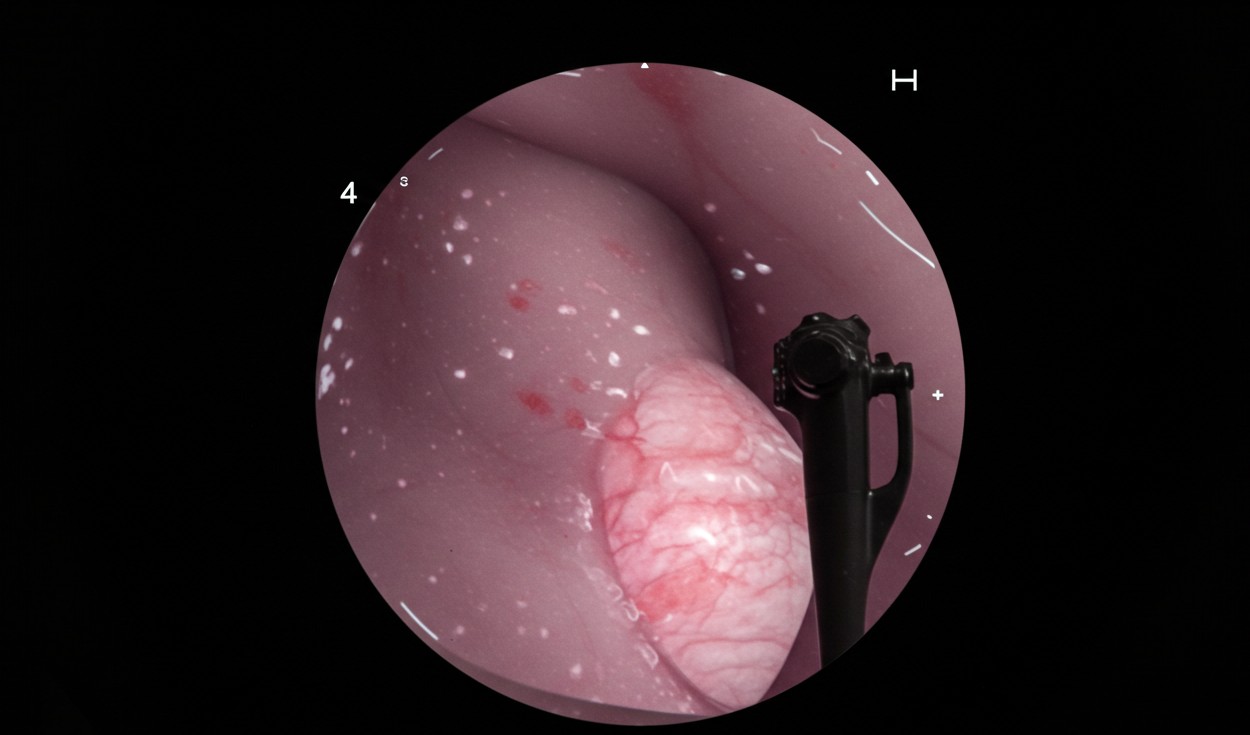

• 검진 방법: 위내시경 권고 (기본 검진 방법으로 확정)

이는 위내시경이 조기 위암 발견에 가장 효과적이라는 국내외 연구 결과를 반영한 것입니다.